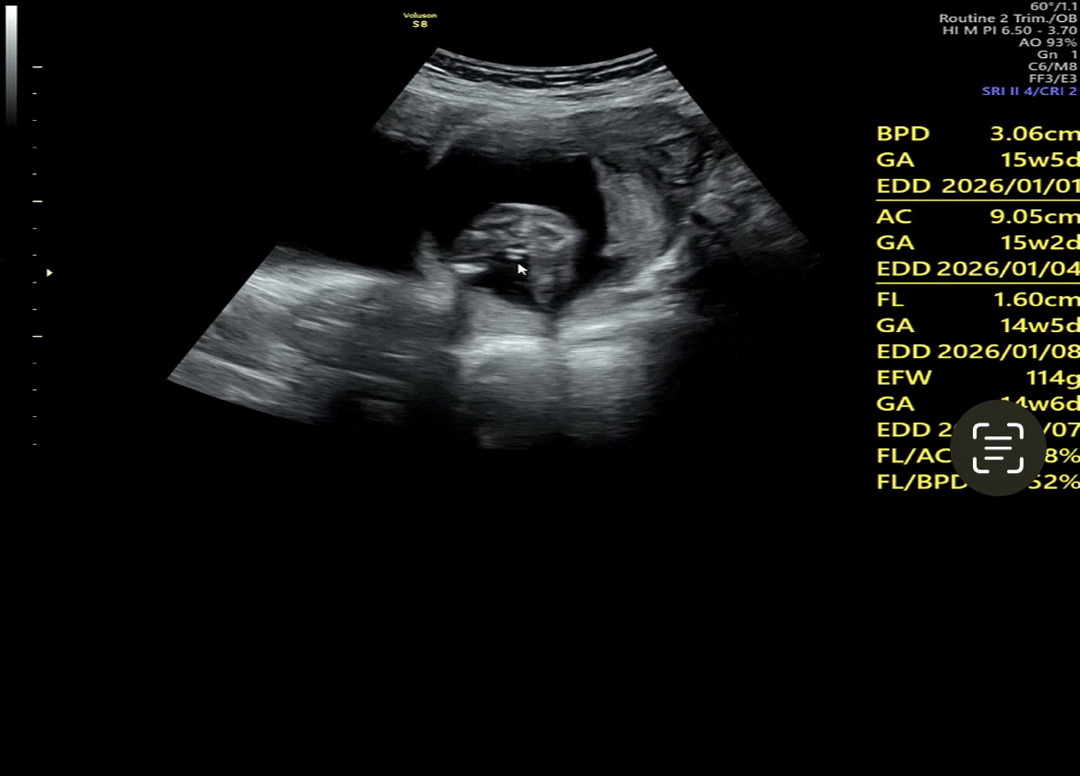

빼박 아들일까용??

의사쌤도 아들이라 하시긴 했는데 딸로 변할가능성은 없어보이나용??

삼각점 있는거 보니 아들 맞네용!